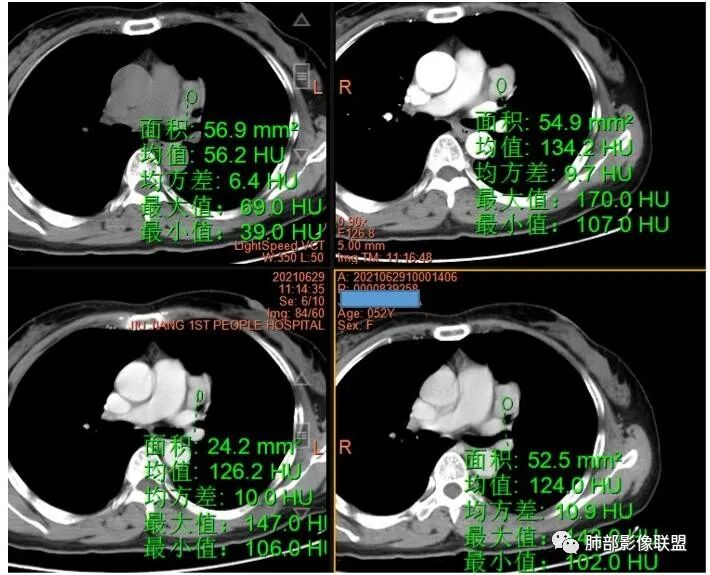

2.左上纵隔肺门夹角处孤立实性密度结节影,边界清楚浅分叶,密度均匀,未见液化、分隔及钙化。

3.动脉期起显著强化并延续至静脉期,强化程度均低于同期胸主动脉。病灶弧形推压左上肺动脉,毗邻左肺上叶支气管但未见侵蚀及突入,相应支气管未见狭窄。